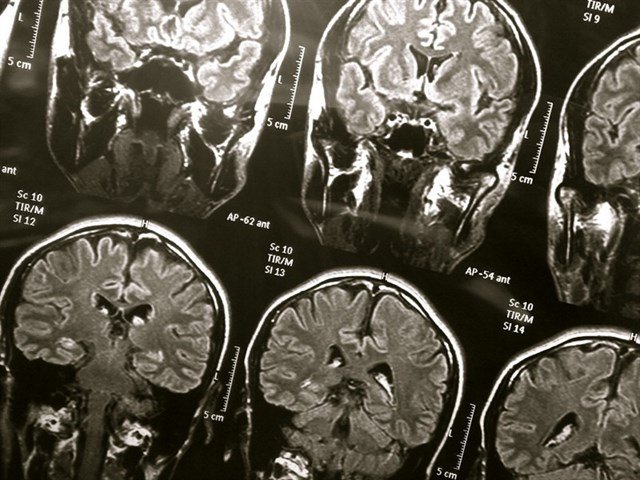

Una técnica de imagen mide la toxicidad de las proteínas de Alzheimer y Parkinson